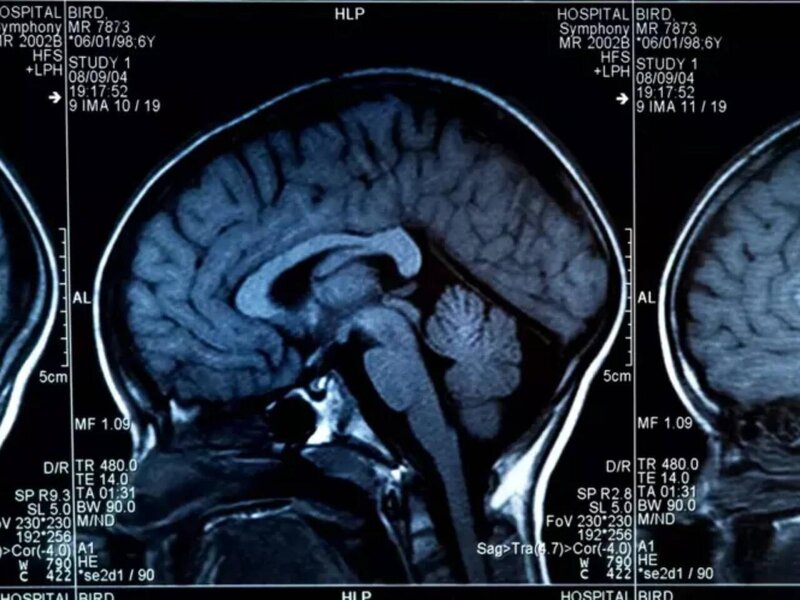

Beyni məhv edən qidalar açıqlandı - Hər gün yeyirik

Beynin sağlamlığını təhlükəyə atan 8 qida açıqlanıb.

Milli.Az xəbər verir ki, aşağıdakı qidaların çoxluğu beynin sürətini zəiflədir.